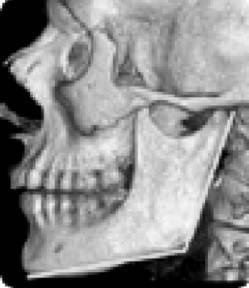

Еще одно сообщение Phys-Org: руководитель службы пластической и реконструктивной хирургии в американской университетской клинике Говард Лэнгстайн (Howard Langstein) на основании своих многочисленных исследований утверждает, что с возрастом происходит изменение угла нижней челюсти (показанные желтым цветом), длина и высота самого тела челюсти (рис. 10).

Иллюстрация к книге — Биогимнастика для лица: система фейсмионика [i_013.jpg]

Рис. 10. Череп молодого человека

А поскольку нижняя челюсть является основной костью лицевой части лица, любые ее изменения влияют на общий вид лица.

Внешне это проявляется в том, что его нижняя часть приобретает более вялые очертания, мягкие ткани провисают, овал теряет свою четкость, снижается тонус кожи щек, подбородка и шеи, в результате чего очертания лица приобретают характерный возрастной вид. Далее Г. Лэнгстайн добавил: «Хотя врачи всегда знали, что кости со временем меняются, но как это проявляется с возрастом – не смогли оценить до конца».